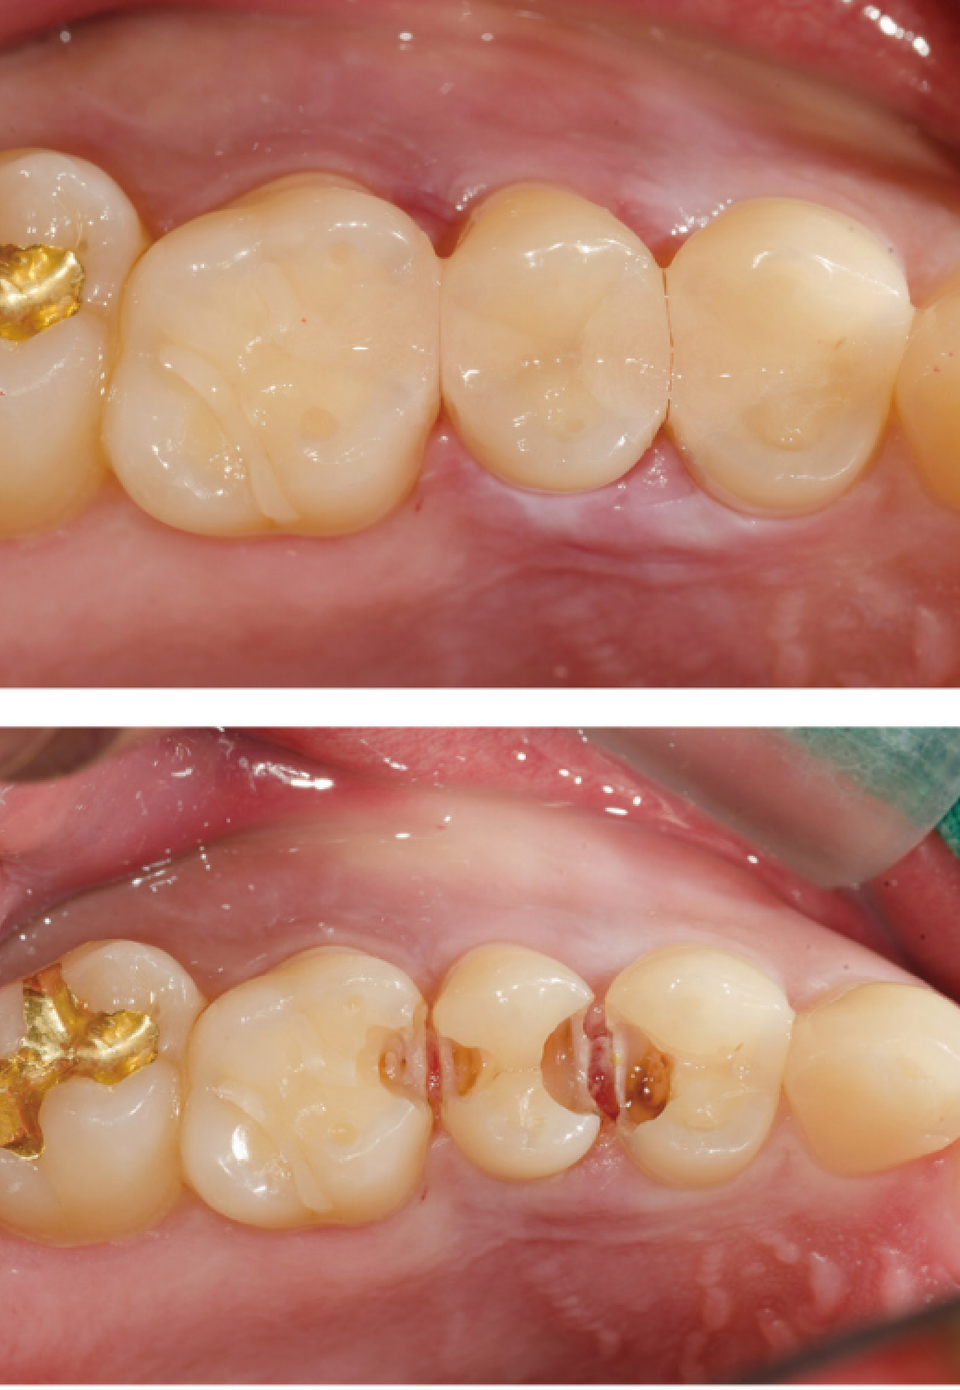

#14~#16 레진 충전

왜 이런 과정을 사진으로 기록할까? 개원한 치과의사는 누구의 간섭도 받지 않고 자신의 양심과 임상능력을 따라 진료한다. 임상 과정을 사진으로 기록하고 정리하는 과정에서 자신의 부족한 점이 드러난다. 최종 치료결과가 좋을 때는 자신감과 직업적인 보람을 얻기도 한다.